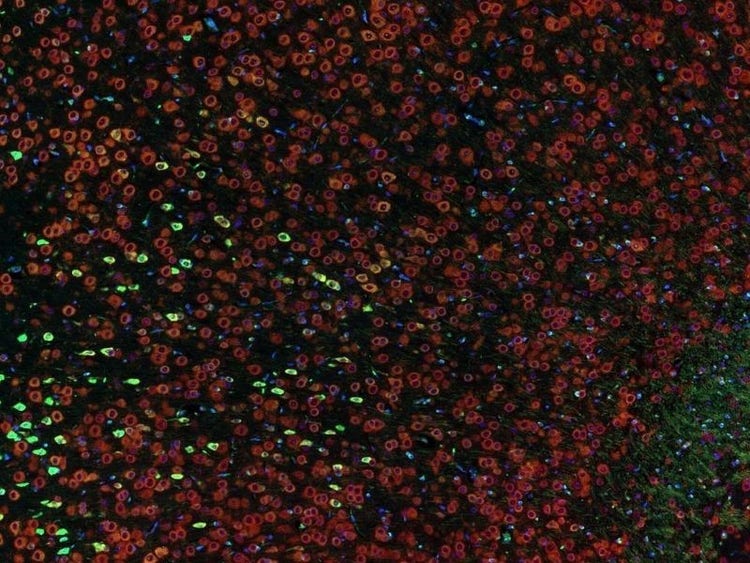

Fluorescence imaging of a mouse brain

Cette vue d’un cerveau de souris est en réalité constituée par l’assemblage d’une multitude d’images prises par imagerie de fluorescence.

Le scientifique britannique Sir George G. Stokes a d’abord constaté que la fluorine minérale devenait fluorescente lorsqu’elle était éclairée par une lumière ultraviolette, et il a inventé le mot « fluorescence ». Stokes a remarqué que la lumière fluorescente présentait des longueurs d’onde supérieures à celles de la lumière d’excitation, un phénomène aujourd’hui connu sous le nom de « déplacement de Stokes ». La microscopie de fluorescence est une excellente méthode pour étudier une matière qui peut devenir fluorescente soit sous sa forme naturelle (appelée fluorescence primaire ou autofluorescence), soit lorsqu’elle est traitée avec des produits chimiques qui peuvent devenir fluorescents (appelée fluorescence secondaire).